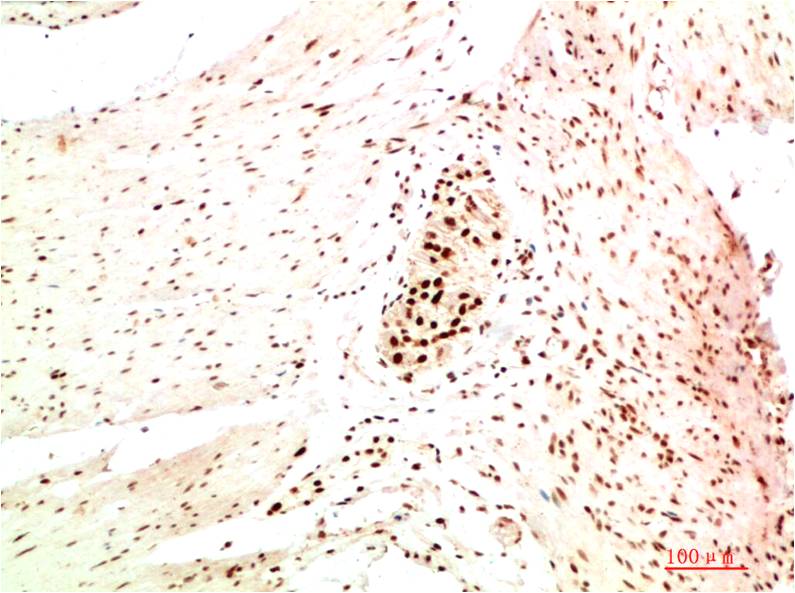

Immunohistochemistry analysis of paraffin-embedded Human Colon Carcinoma Tissue using HP1 alpha antibody.High-pressure and temperature Sodium Citrate pH 6.0 was used for antigen retrieval. |